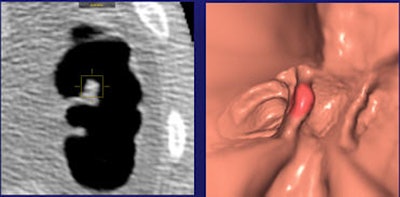

![]() |

| In a 59-year-old man, a 6-mm sessile polyp on a haustral fold visible only on the prone scan was missed by the radiologist but found by CAD. Histology: hyperplastic. All images courtesy of Dr. Daniele Regge. |